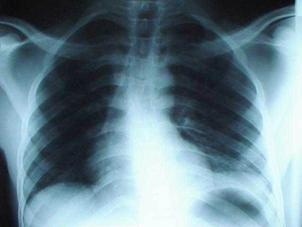

Pneumotorace simplu stang Pneumotorace

simplu stang

Pneumotorace